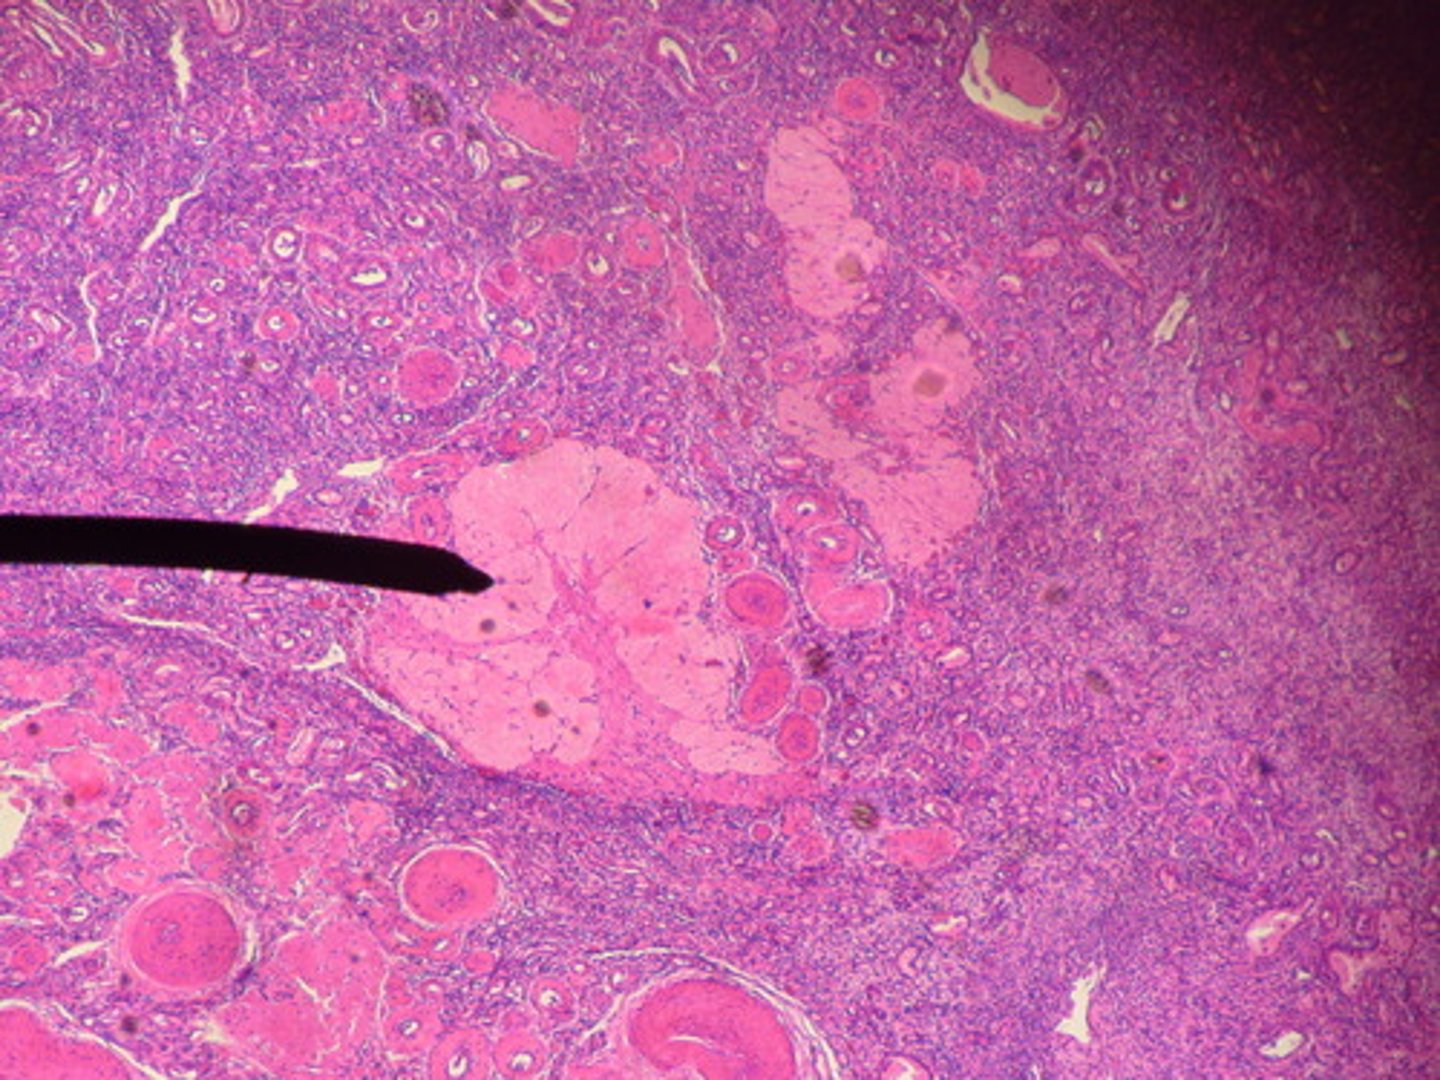

leydig cell

lobule

primary spermatocyte

rete testis

secondary spermatocyte

seminiferous tubule

red

spermatid

spermatogonium

sperm

black lines

nurse cell

tunic albuginea